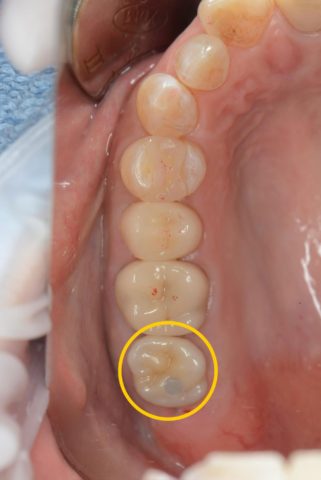

“右上の1番奥の歯を他院で抜歯と診断されだが残したい”という主訴で来院されました。

検査診断の結果、この歯は抜歯でIPを行うことになりました。

今回のケースは歯に歯茎が乗ってきているので、歯茎を切って下げることで歯を出す処置(歯冠長延長術)が必要です。

しかし歯茎がかなり覆い被さってるので、フェルールを獲得するためには7mm歯茎を切って下げないといけないのですが、そうなると歯の根っこが露出してしまうため、保存不可能という診断です。